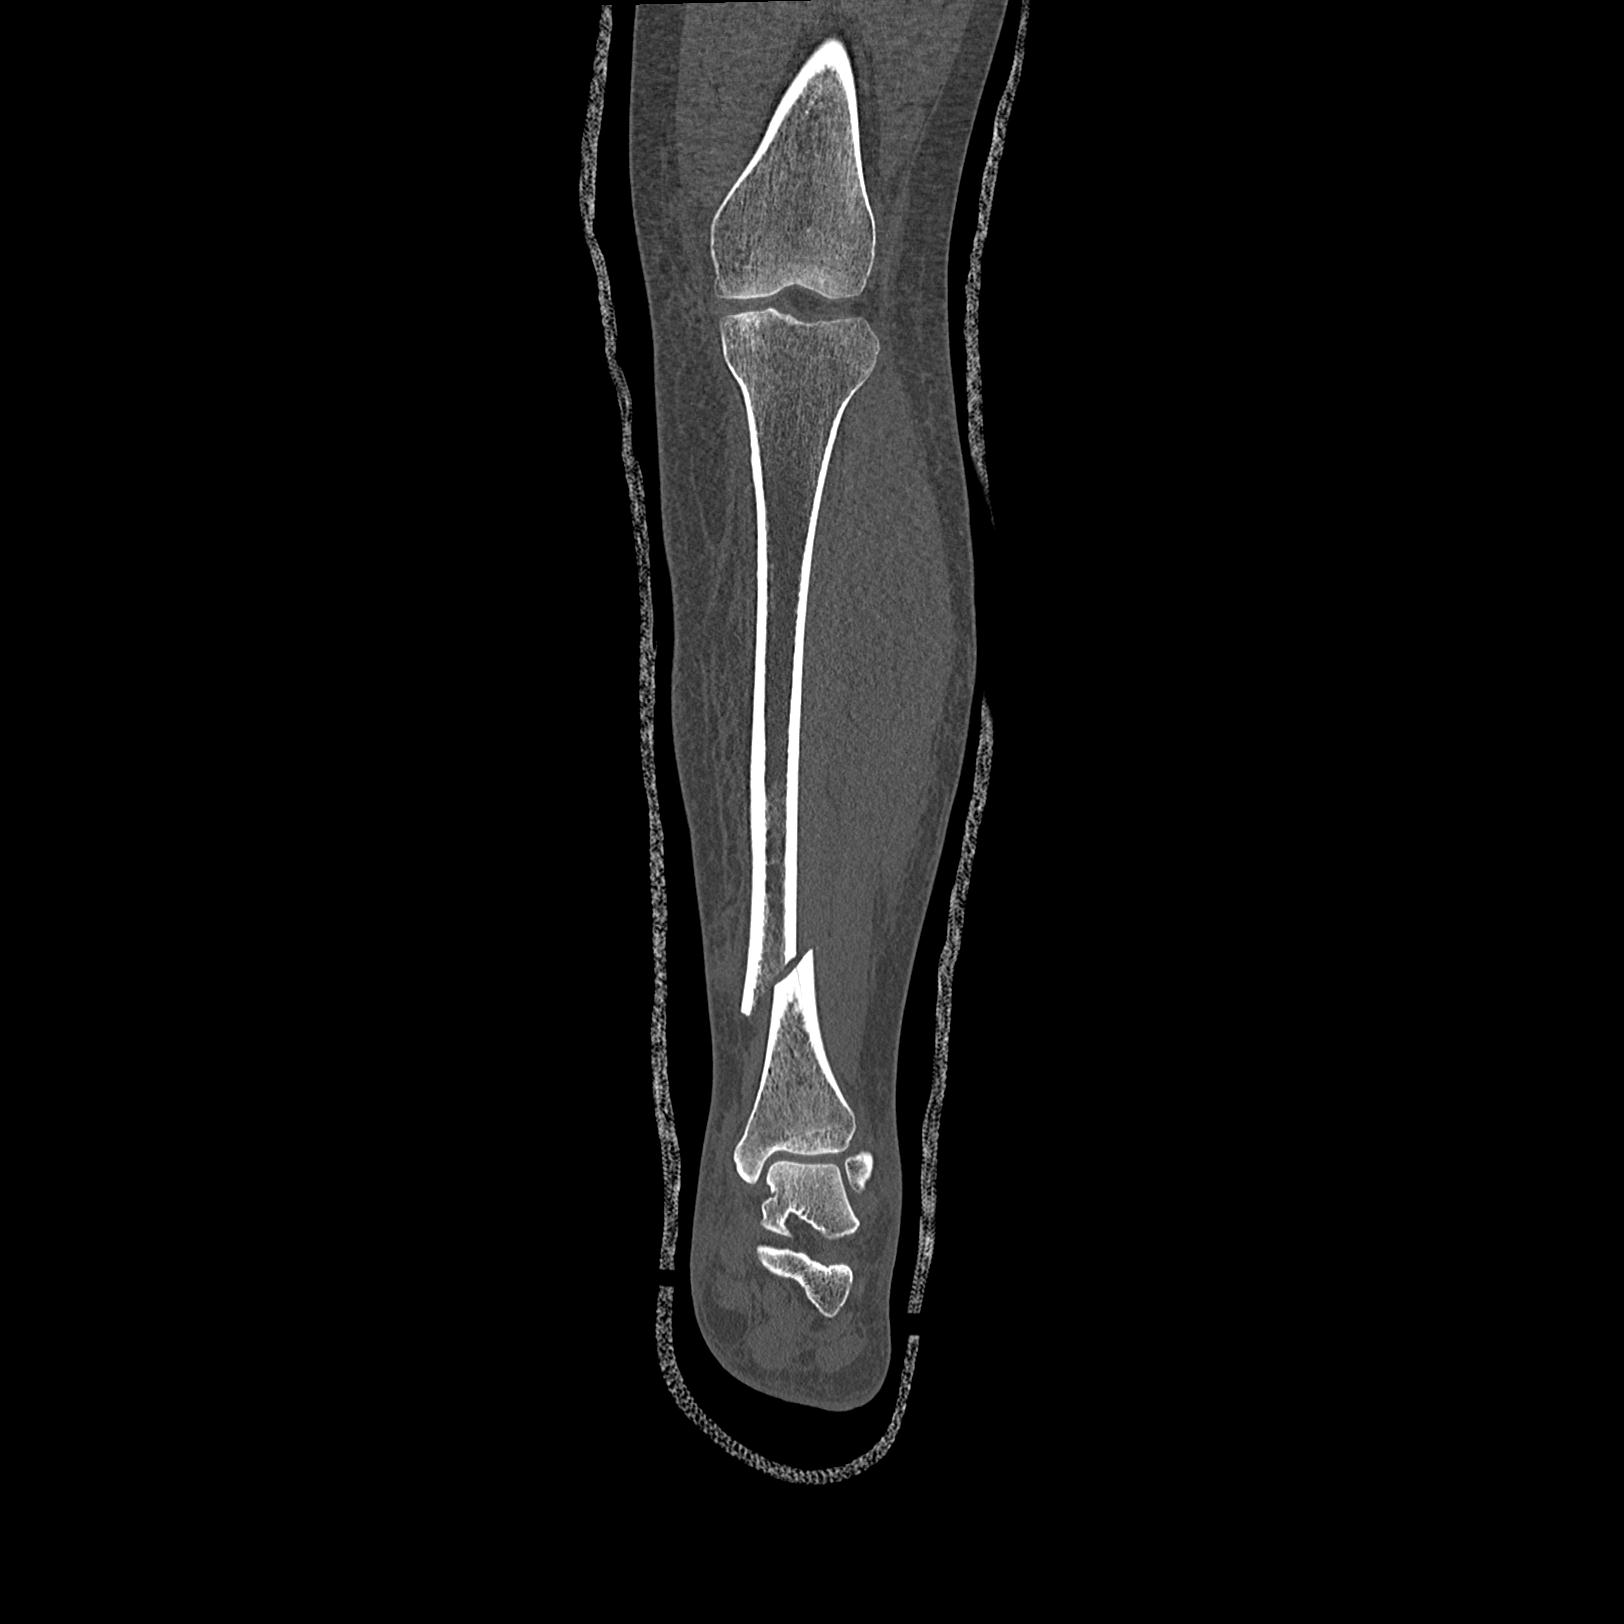

102803 1/12(キウスなし) 1/27 左下腿 4R 30歳女性 左脛骨軸内釘